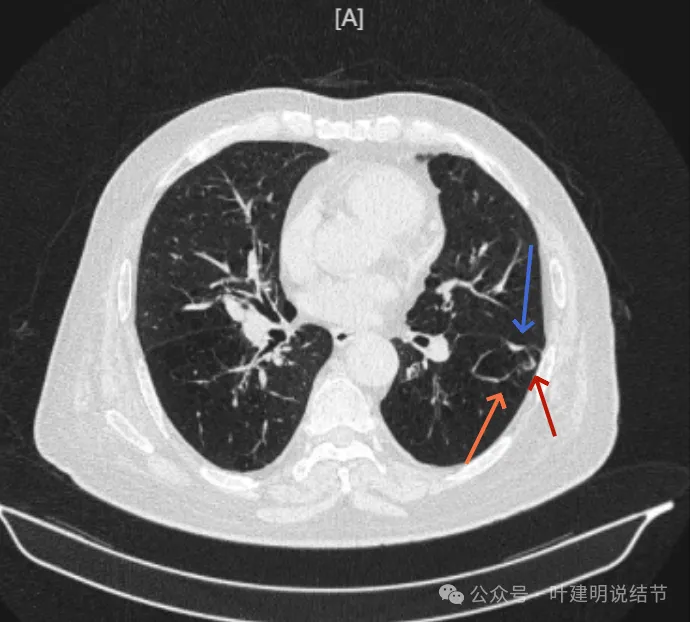

先看2024年6月的影像:

靠叶裂侧密度高、实性,灶内空腔多房,有微小血管走向并进入病灶的囊壁内,叶间裂有受牵拉。

囊壁明显厚薄不均,内壁也不光滑,而整体轮廓与边界却较为清楚。

部分边缘有细毛刺样征、中间密度低些,边上有囊腔,有的地方有少许磨玻璃成分,见到有小血管多处进入病灶。